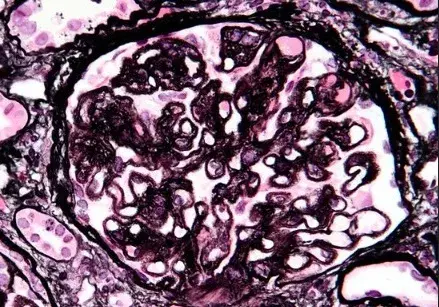

Es posible identificar un glomérulo con rotura de la membrana basal glomerular, con crecimiento celular en el espacio de Bowman (flecha blanca), células gigantes multinucleadas (estrella) y ruptura de la cápsula de Bowman (flecha negra) (tinción PAS; 400×). PAS, ácido periódico-Schiff.

La biopsia renal reveló GN (glomerulonefritis) crescéntica necrotizante difusa sin hipercelularidad endocapilar. Algunos raros glomérulos contenían células gigantes multinucleadas.

La evaluación de la microscopía de luz puede ayudar en la diferenciación entre casos de **GN por anti-MBG** y casos de **GN-ANCA**, ya que en la GN por anti-MBG no se observa hipercelularidad endocapilar y se puede identificar la presencia de células gigantes multinucleadas. Estas células gigantes multinucleadas resultan de la naturaleza explosiva y la rápida destrucción de los glomérulos observada en la anti-MBG.

Por lo tanto, la presencia de lesiones crescénticas temporalmente similares y células gigantes multinucleadas en la microscopía de luz (MO) puede ayudar en el diagnóstico temprano."